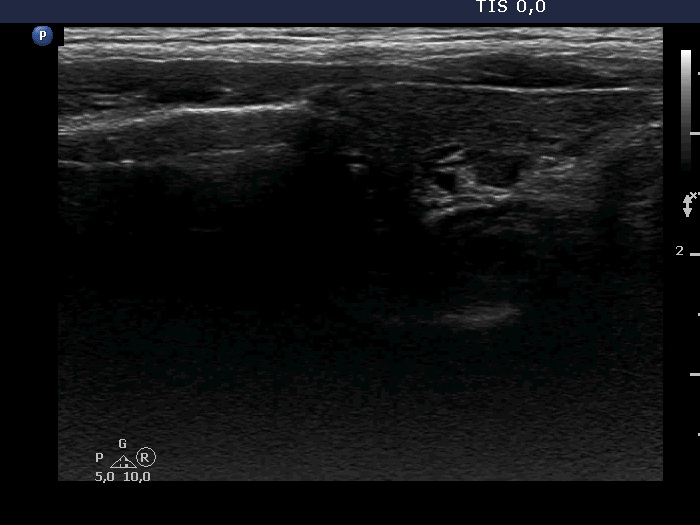

The borders of the nodule - case 1036

30 months after the initial examination (ultrasonographic picture 5)

Left lobe, longitudinal scan.